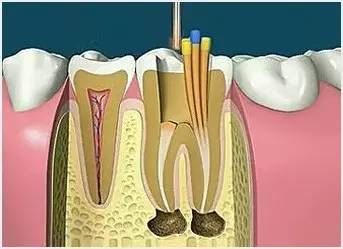

6、根管充填

封闭整个根管系统、堵塞主根管和侧副根管出口、防止微生物和液体的渗漏。无论是侧方加压法还是垂直加压法,应做到根管充填致密,根管充填后X线片上无根管腔隙,也不能超出根尖孔。

7、根管打桩

因牙体缺损过多,导致牙的强度(承受力量的性能)大幅度下降,不能很好地承受咀嚼力量。打桩的目的是增加牙根及牙冠的强度,增加患牙的稳固。